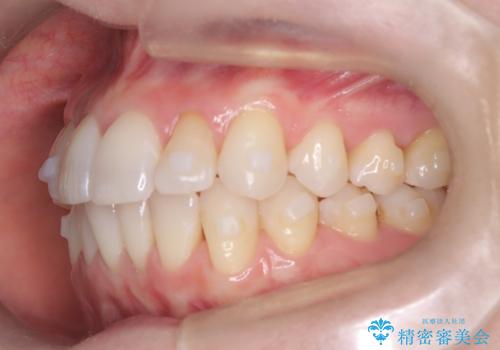

矯正後の後戻りで前歯にガタツキができてしまった インビザラインで改善

- 子どものときにワイヤー矯正をしていたが、後戻りによって前歯のガタツキが気になってきたとのことで来院されました。

アライナー矯正希望だったため、インビザラインによる治療を行いました。

- 7ヶ月

- 60.5万円費用は治療当時の料金となります